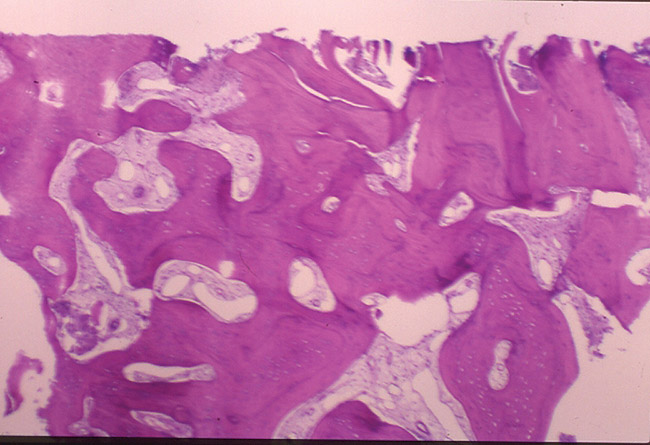

Figure 2d  The histology report included the presence of viable bone consisting of anastomosing trabeculae surrounding Haversian systems

Figure 2d

Figure 2e  The bone formation is primarily lamellar. Osteocytes were present within the lacunae. Woven bone was observed in the dense connective tissue. Fragments of calcified debris are admixed with the periphery of this decalcified specimen. The viable bone exhibits prominent resting and reversal lines. A diagnosis of viable sclerotic bone was made.

Figure 2e

The histology report included the presence of viable bone consisting of anastomosing trabeculae surrounding Haversian systems. The Haversian systems contain connective tissue with variably sized, endothelial-lined vascular spaces. The bone formation is primarily lamellar. Osteocytes are present within the lacunae. Abundant fibrous connective tissue is present at the periphery of this soft-tissue specimen, and woven bone is observed in the dense connective tissue. Fragments of calcified debris are admixed with the periphery of this decalcified specimen. The viable bone exhibits prominent resting and reversal lines. A diagnosis of viable sclerotic bone was made.